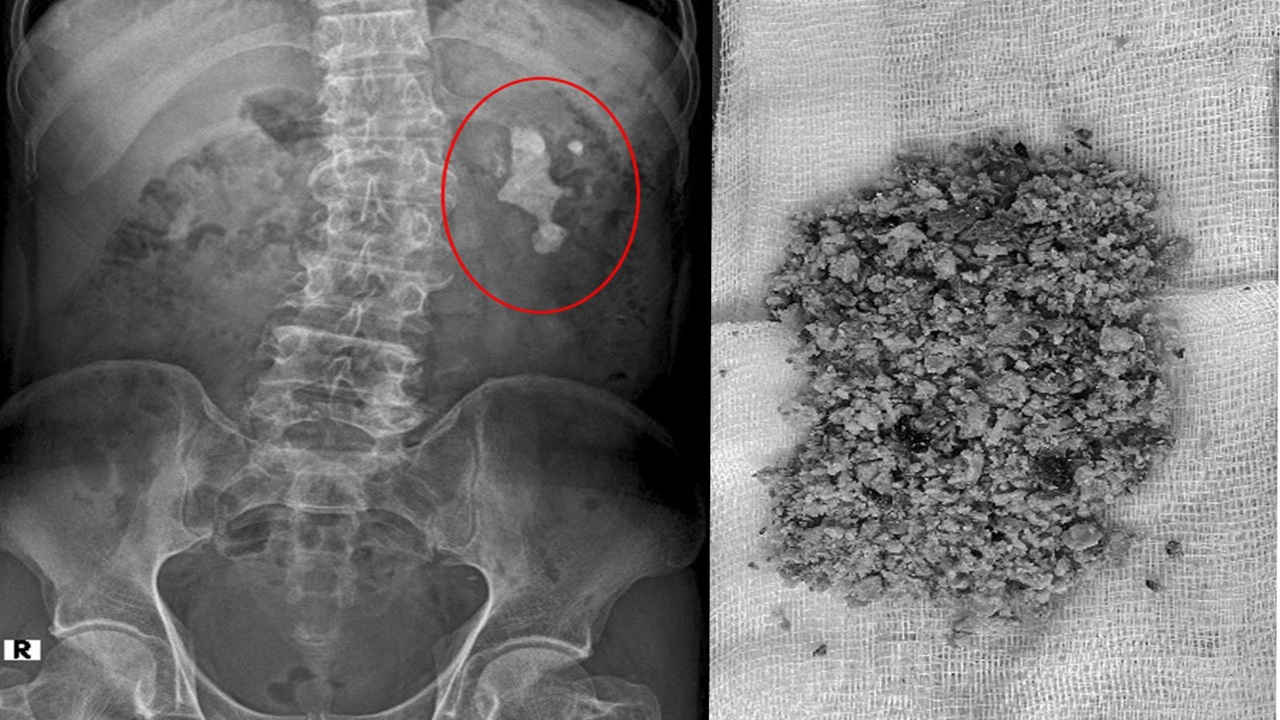

Sỏi thận là những viên cứng, hình thành từ các chất khoáng và muối trong nước tiểu. Các chất này không được cơ thể xử lý hoặc loại bỏ kịp thời, dẫn đến sự hình thành các viên sỏi nhỏ, có thể tồn tại trong thận trong một thời gian dài mà không gây ra triệu chứng rõ rệt. Tuy nhiên, khi sỏi di chuyển vào niệu quản hoặc gây tắc nghẽn dòng nước tiểu, chúng có thể gây ra những cơn đau dữ dội.

Tán sỏi ngoài cơ thể: Đây là phương pháp sử dụng sóng siêu âm để phá vỡ sỏi thành các mảnh nhỏ, giúp chúng dễ dàng được đào thải ra ngoài qua nước tiểu.